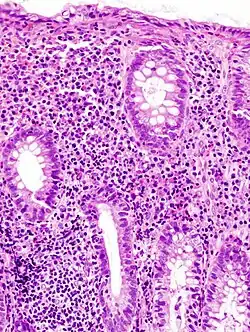

Die Diagnose Colitis ulcerosa kann nur durch eine Darmspiegelung (Koloskopie) mit Probeentnahmen (Biopsie) und anschließender feingeweblicher (histologischer) Untersuchung gestellt werden.

- Bei einem milden Verlauf kommt es zur ödematösen Schwellung der Darmschleimhaut.

- Bei mittleren Verlaufsformen kommt es zu leichten Blutungen und Geschwürsbildungen.

- Bei schweren Verläufen kommt es zu großflächigen Geschwürsbildungen, die zum Verlust des Reliefs und zur Schleimhautabflachung führen. Durch überschießende Regeneration kommt es zur Bildung von Pseudopolypen. Feingeweblich (histologisch) fallen Lymphozyten und Histiozyten auf, während die Zahl der Becherzellen stark vermindert ist. Als typisch, wenn auch nicht beweisend, gelten Kryptenabszesse.